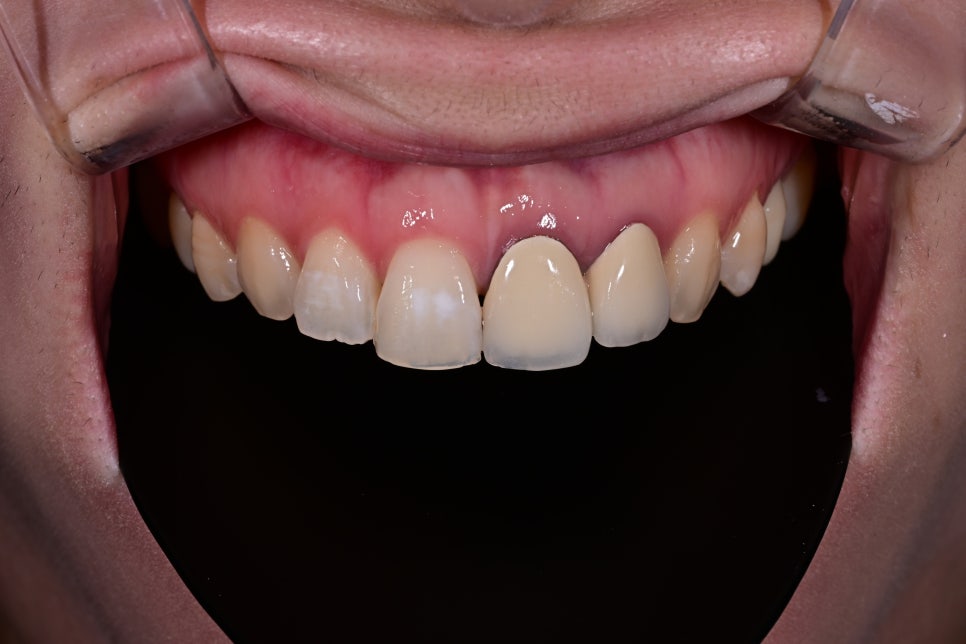

Comparison before and after treatment

<BEFORE>

<AFTER>

The patient first mentioned the naturalness of the color.

The existing crown had a noticeable brightness difference compared with the surrounding teeth,

which she described as looking like an “overlay,”

but the newly designed OBZERO looked natural even without makeup,

and she said it felt like her own teeth.

In addition, the incisal edge gained natural translucency and volume,

and the harmony with the lip line when smiling improved significantly.

She also said it looked more natural in photos.